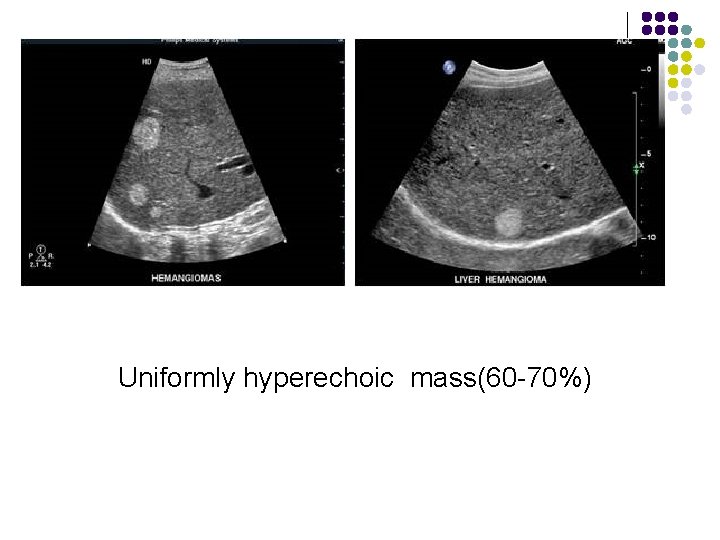

Ultrasonic features of Hepatic hemangioma l l l Uniformly hyperechoic mass(60 -70%) Inhomogeneous hypoechoic mass (up to 40%) Homogeneous(58 -73%) /heterogeneous May show acoustic enhancement(37 -77%) Unchanged in size/appearance(82)on 1 -to-6 year follow-up No Doppler signals/signals with peak velocity of <50 cm/cm

。 Uniformly hyperechoic mass(60 -70%)